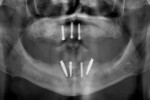

During the first clinical visit, guided surgery was performed following a strict surgical protocol in which four dental implants were placed (NobelGuide®, Nobel Biocare) in the mandible.13-15 Primary stability greater than 35 Ncm was achieved (Figure 3). After implant placement and profiling of the crestal bone, two straight and two 30-degree angled multi-unit abutments were torqued onto the implants.13-15 Temporary abutments were connected on the multi-unit abutments, and rubber dam was used to isolate the underlying soft tissue.10 After the mandibular denture was hollowed out, the temporary abutments were picked-up with acrylic resin using the conversion prosthesis technique.10 While the conversion prosthesis was being trimmed and contoured in the laboratory, two multi-unit abutment-level impressions were taken: one conventional impression (followed by digitization with a laboratory scanner) and a digital one with an IOS system (TRIOS®, 3Shape, 3shape.com). However, the impression used for fabrication of the final prosthesis was the conventional one after digitization with a laboratory scanner; this is because full-arch digital implant impressions with IOSs were not scientifically validated in 2016 during the treatment of this case.